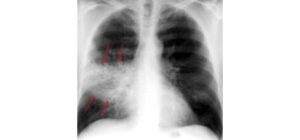

Giãn phế quản

Ông T 57 tuổi đến khám tại phòng khám Phổi Việt theo chương trình Hội chẩn chuyên môn bệnh hô hấp khó trị vì một nỗi trăn trở là ông thỉnh thoảng lại ho ra đàm vướng máu, thường là đàm màu trắng có dính dây máu, nhưng cũng có khi máu đỏ tươi lượng […]